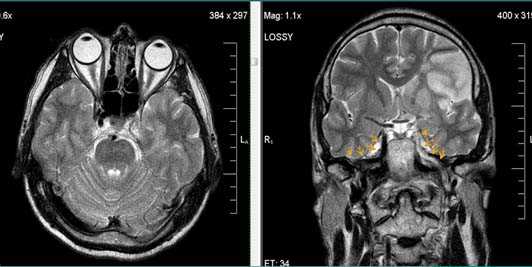

Первые часы ОНМК. Изменения в области правого островка демонстрирует только программа DW insult.

Бассейн кровоснабжения левой верхней мозжечковой артерии, острая стадия НМК.

Зона подострого ишемического НМК, в бассейне правой средней мозговой артерии. В режиме Т1 визуализируется симтом «вуалирования»- изоинтенсивность МР-сигнала.

Подострая стадия ишемического НМК. При внутривенном контрастировании определяется накопления КВ в бороздах на уровне зоны ишемии (гиральный тип усиления).

Зона хронического ишемического НМК, в бассейне левой задней мозговой артерии.

Ишемическое ОНМК, ствол мозга (подострый период)

Кортикальное ишемическое НМК

Лакунарное ишемическое ОНМК на фоне хронической сосудистой недостаточности.

Некоторые инфаркты при дисциркуляторной энцефалопатии протекают бессимптомно. Это «немые» инфаркты, которые, как правило, локализуются в глубоких отделах мозга и диагностируются только при МРТ. Этот случай показывает возможности выявление очага ограниченного ишемического ОНМК базальных ядер слева на фоне хронической ишемии.

Выраженная сосудистая энцефалопатия с наличием множественных очагов хронической ишемии, лакунарных постишемических кист. Программа ДВИ четко показывает фокус острого ОНМК в базальных ядрах справа на фоне лейкодистрофии.

Ишемической инсульт в бассейне левой средней мозговой артерии. Отсутствие феномена пустоты потока на уровне интракраниального отдела левой ВСА (признаки замедления кровотока).

Ишемический инсульт в ВББ слева. Отсутствие феномена пустоты потока на уровне экстракраниального отдела левой позвоночной артерии (признаки замедления кровотока).

Постишемическая лакунарная киста с перифокальным глиозом (средняя треть corona radiata справа)